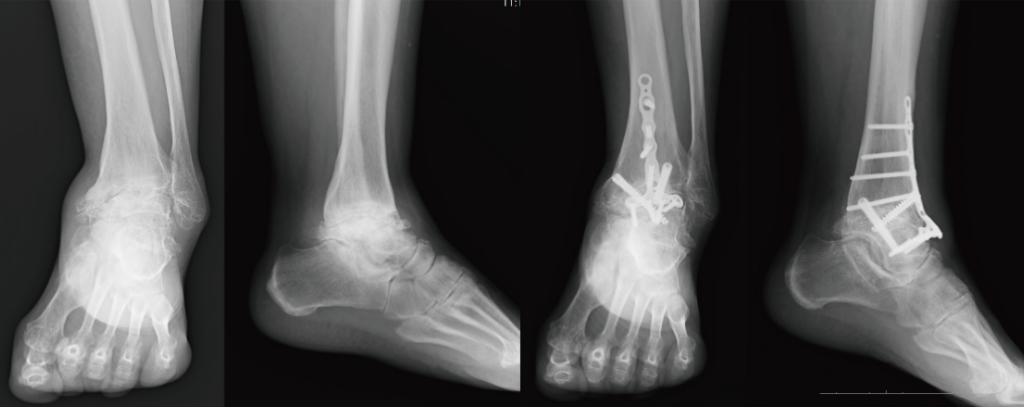

変形が進行すると足首の動きが徐々に悪くなり歩行困難になったりすることもあります。診断としては症状や所見、外観から変形性足関節症を疑いX線像で診断します。特に体重をかけた状態でX線撮影を行い程度を把握します。場合によってMRIやCTも実施します。

↓観血的関節固定術(他家骨移植併用例)